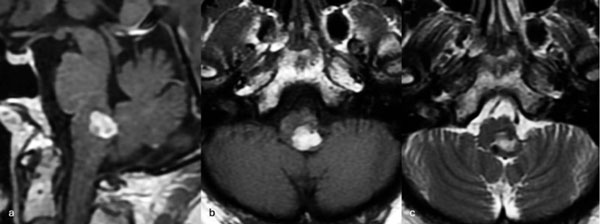

Figura 9. RM preoperatoria de encéfalo. Se evidencia una lesión única intraaxial bulbotrigonal izquierda, que contacta la mitad inferior del piso del cuarto ventrículo, hiperintensa en T1 y T2, con vacíos de flujo que impresionan provenir de una malformación del desarrollo venoso, lo que sugiere una malformación cavernomatosa. A) Imagen en corte sagital ponderada en T1 posterior a la administración de gadolinio. B y C) Imágenes en corte axial ponderadas en T1 y T2, respectivamente.

Figura 11. RM postquirúrgica de encéfalo. Se evidencia una exéresis completa, sin daño del parénquima adyacente. A) Imagen en corte sagital ponderada en T1 posterior a la administración de gadolinio. B y C) Imágenes en corte axial ponderadas en T1 posterior a la administración de gadolinio y T2, respectivamente.